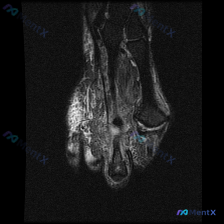

看到这个踝关节MRI的读片资料,整理了完整的分析思路分享给大家。 病例影像基本信息 这是一张踝关节冠状位T2加权MRI,核心发现是距骨穹窿外侧的软骨异常,先把影像观察结果整理清楚: 1. 骨骼系统:胫骨、腓骨、距骨骨皮质连续,没有骨折或骨质破坏;但距骨穹窿外侧可见片状T2高信号,提示局部骨髓水肿 2...

看到一份踝关节MRI软骨异常的读片需求,整理一下病例信息和分析思路和大家分享: 一、病例影像基本信息 本次读片的影像为踝关节MRI-冠状位T1序列,核心问题是评估发现的软骨异常。 二、影像核心表现整理 1. 骨骼结构: 胫骨远端、距骨、腓骨远端结构完整,骨髓信号均匀,无广泛骨髓水肿或肿瘤浸润征象;踝...

刚整理完一份踝关节MRI读片资料,病灶很典型,分享一下读片思路给大家参考。 病例核心影像信息 影像为踝关节冠状位T2加权单帧图像,清晰度可,主要发现如下: 1. 核心异常:距骨穹顶内侧可见局灶性不均匀T2高信号,边界相对清晰,提示该区域骨髓水肿;距骨穹顶关节面不连续,软骨下骨质轮廓稍不平整,信号增高...

最近看到这例踝关节MRI读片讨论,问题是「图像中能观察到什么软组织液相关改变」,整理一下完整分析思路,分享给大家。 一、病例影像核心信息 这是踝关节MRI冠状位T2加权图像,核心发现如下: 1. 骨结构改变:胫骨远端、距骨、跟骨显影清晰,距骨穹窿内侧关节面可见局灶性高信号改变,边界清晰,呈楔形凹陷状...